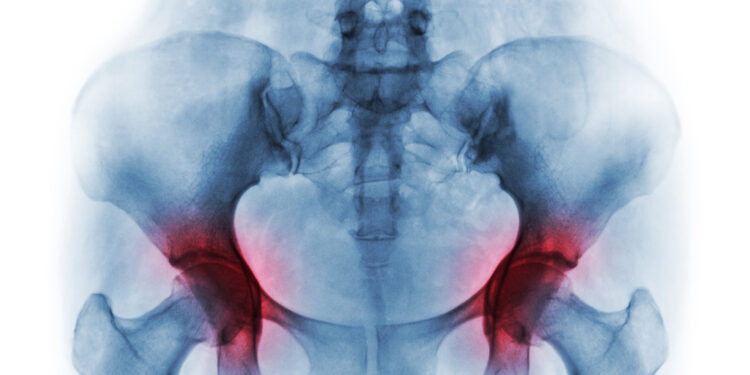

Kaip nustatoma osteoradionekrozė?

Dažnai ši liga išryškėja tik praėjus ilgam laikui nuo pirminio gydymo. Įtarus osteoradionekrozę gydytojas apžiūri galvos ir kaklo sritis, gali paprašyti informacijos apie gautą radiacijos dozę iš Jūsų gydymo istorijos.

Kokie tyrimai gali būti taikomi?

- dantų rentgenogramos,

- kompiuterinė tomografija (KT) žandikauliui,

- biopsija, padedanti atskirti, ar nėra išplitęs vėžys.